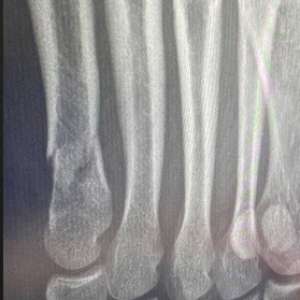

После месяца в гипсе вот такой результат(второе фото)

Ей зафиксировали ногу и сказали не нагружать ее

Вопрос:все ли сраслось и срастется хорошо?